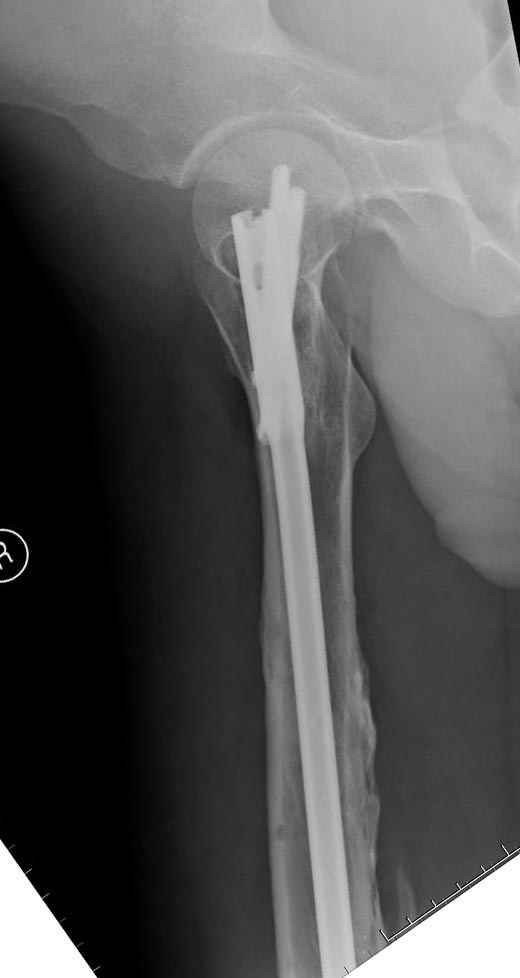

Замена реконструктивного штифта “Custom made Nail” с антибиотиком (рис №5, №6),

после промывки канала с рассверливанием внутреннего кортекса, через 4 недели антибиотический штифт удалили, оспалителный процесс остановлен и бедро сросся.